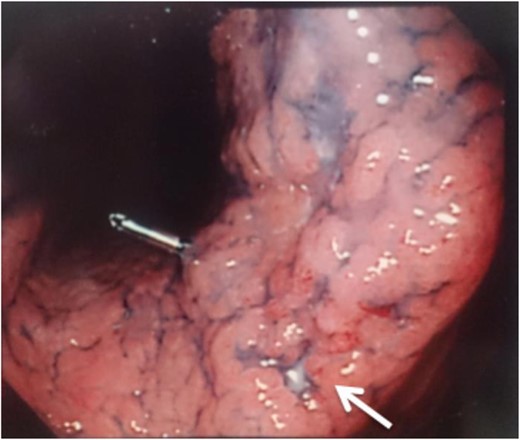

Two years and 3 months after esophagectomy, he complained of pain in the left shoulder. A mass was found between the trapezius and supraspinatus on CT and magnetic resonance imaging (Fig. 3). 18F-fluorodeoxyglucose (FDG) positron emission tomography (PET) demonstrated increased levels of FDG accumulation in the left shoulder. Needle biopsy demonstrated class V (unclear type of carcinoma) disease. Therefore, we performed tumor dissection for muscle metastasis, and the histopathologic diagnosis was SCC. The patient thus underwent adjuvant chemotherapy with S-1 (80 mg/day) administered 4 weeks on/2 weeks off schedule for 1 year.

A hyperintensity mass between the trapezius and supraspinatus on T1-weighted magnetic resonance imaging (A, axial view; B, coronal view).